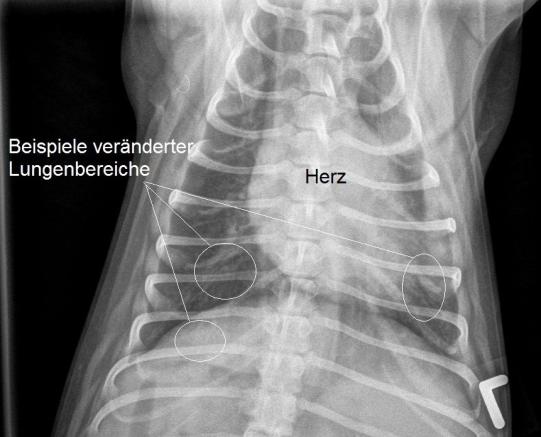

Aus diesem Grund werden nun Lungenröntgen angefertigt. Auf den Bildern sind leichte bis mittelgradige, diffus verteilte Lungenverschattungen vom sogenannt bronchointerstitiellen Typ erkennbar. Als mögliche Ursachen kommen bei diesem Typ Lungenveränderung neben einer chronischen bakteriellen Bronchitis insbesondere ein Infekt mit Lungenwürmern in Frage. Da ein Breitspektrumantibiotikum keine Verbesserung des Hustens bewirkt hatte, scheint ein Lungenwurmbefall nun sehr wahrscheinlich.